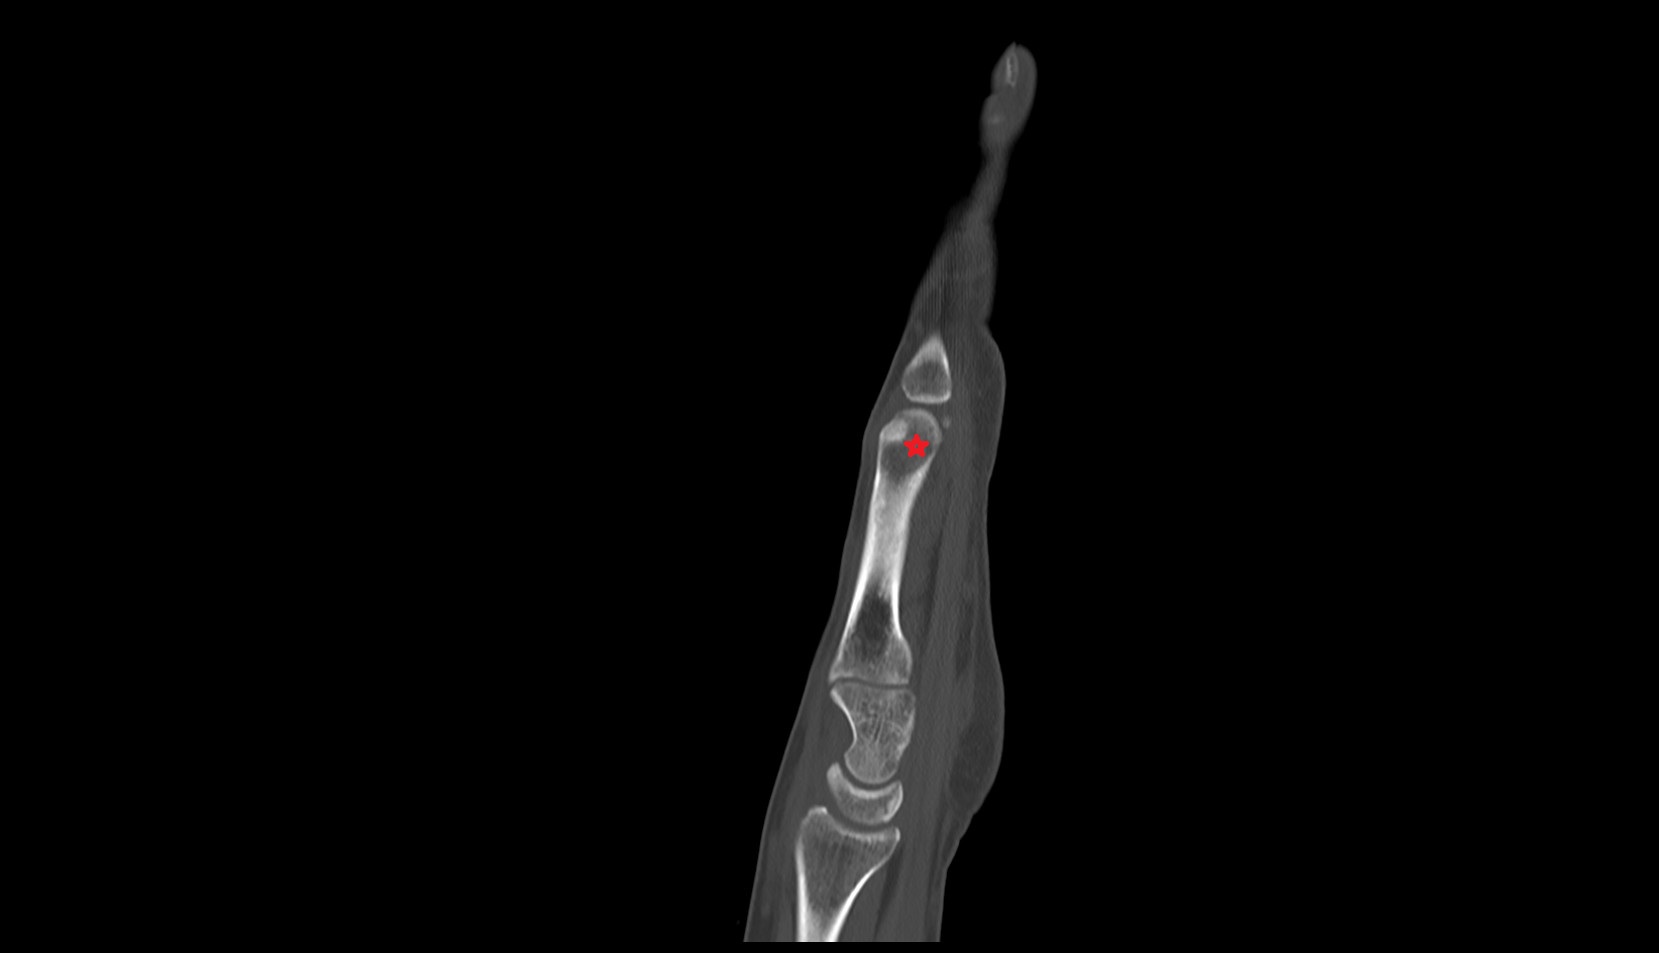

- Cubital tunnel